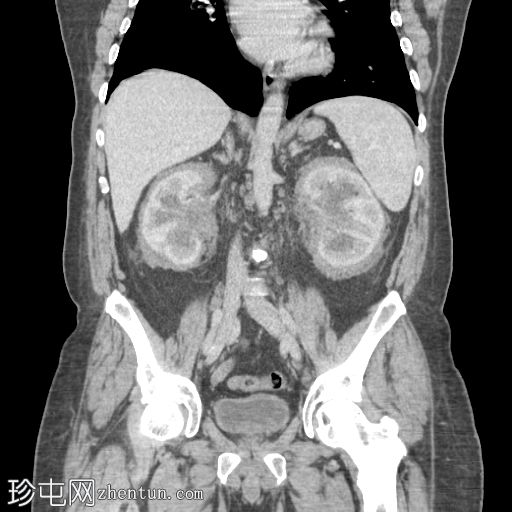

矢状位增强扫描(门静脉期)

肾周可见重度、相对均匀的浸润,呈“毛肾征”。肾积水,但无输尿管积水。

肝、脾、胰腺和肾上腺正常。胆囊正常,无胆管扩张。